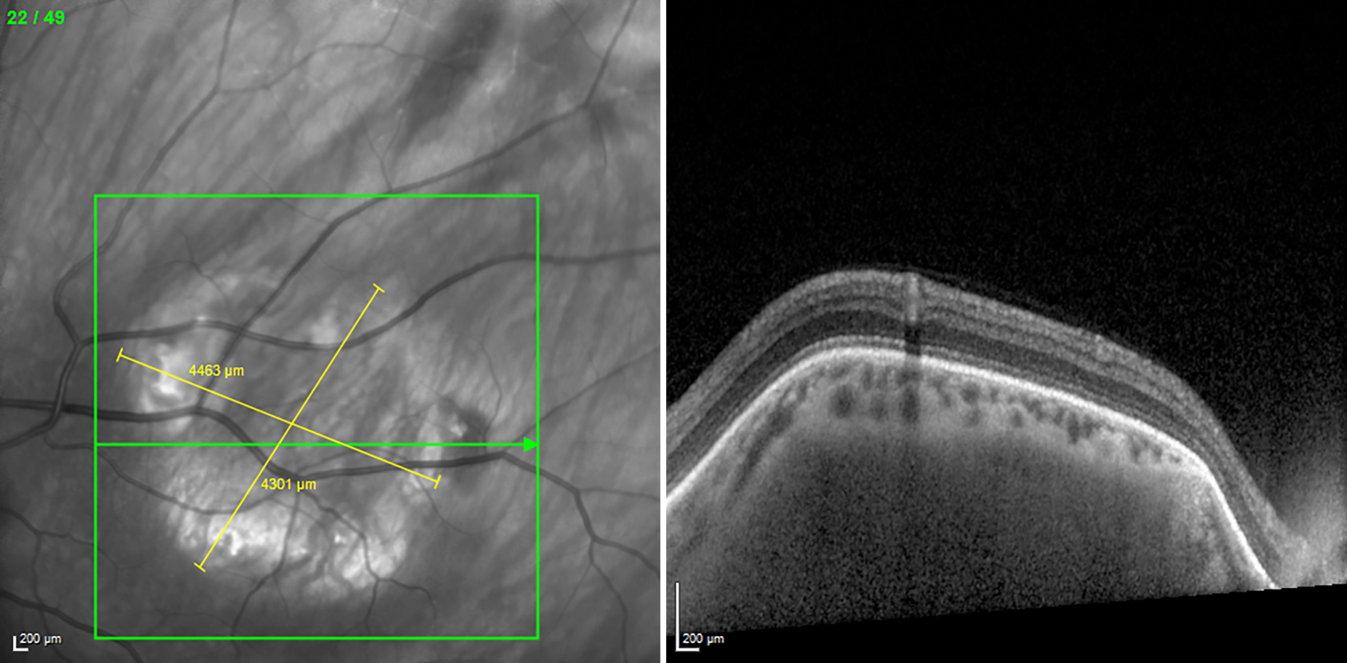

Abb. 4

Sklerochoroidale Kalzifizierungen dargestellt mittels „enhanced depth imaging“ optischer Kohärenztomographie (EDI-OCT). Im Infrarotbild imponieren diese als hyperreflektive Areale, welche ringförmig ausgelegt sind. Die Choroidea erscheint an den Stellen leicht verdünnt

In der optischen Kohärenztomographie (OCT) waren die Befunde für Papille und Makula beidseits unauffällig. Die Papillen waren auch in der Heidelberg Retina Tomographie (HRT) unauffällig. Im Januar 2021 und 2022 wurde jeweils eine Gesichtsfelduntersuchung durchgeführt (Abb. 2), welche jeweils frei sowohl von glaukomatösen als auch den Läsionen korrespondierenden Defekten waren. Die Mean Deviation (MD) betrug am rechten Auge −0,5 dB, am linken Auge −0,4 dB. In der Sonographie zeigten sich die Läsionen als hyperechogene sklerochoroidale Strukturen mit distaler Schallauslöschung (Abb. 3) ohne Hinweis auf eine retrobulbäre Raumforderung. In der Fundusautofluoreszenz (Abb. 1, A2, B2) zeigten sich die Läsionen als hyperfluoreszierende Areale. In der Enhanced-Depth-Imaging-OCT (EDI-OCT) sind die betroffenen Netzhautareale unauffällig, die Choroidea erscheint aber leicht verdünnt (Abb. 4). Mittels internistischer Laboruntersuchung (u. a. Blutbild, Elektrolyte, Leber- und Nierenwerte, Entzündungsparameter und Blutgerinnung) konnte eine systemische Beteiligung ausgeschlossen werden.

Die sklerochoroidale Kalzifizierung ist eine seltene Erkrankung, welche meist als Zufallsbefund während einer Routineuntersuchung beim niedergelassenen Augenarzt bei älteren Patienten diagnostiziert wird [5]. Im Allgemeinen sind die Patienten beschwerdefrei, und die Sehschärfe ist nicht herabgesetzt, da sich die Läsionen in der Peripherie befinden und die Fovea aussparen. Es wurden jedoch schon Fälle beschrieben, in denen auch der N. opticus betroffen ist, was zu einer progredienten und schweren bilateralen Sehverschlechterung führen kann [6]. Die Klassifizierung kann anhand des morphologischen Erscheinungsmuster in der EDI-OCT erfolgen [1]. Die Läsionen sind charakteristisch bilateral vorhanden, auch wenn es manchmal schwierig sein kann, diese fundoskopisch zu detektieren, insbesondere wenn die Läsionen weit in der Peripherie liegen. Hier kann die Sonographie – und als Ultima Ratio die Computertomographie – hilfreich sein, da die Läsionen hier als hyperdense Raumforderung sichtbar werden [4].